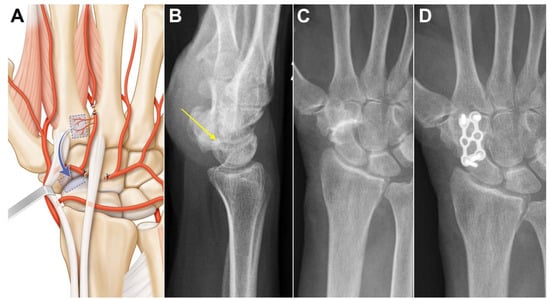

Case 1: A 73-year-old female suffering from long-standing left scaphotrapeziotrapezoidal arthritis. Surgery was proposed after failure of conservative treatment. The patient underwent a scaphotrapeziotrapezoidal bone fusion. A longitudinal incision was made in line with the 2nd metacarpal ray over the carpus. Anastomosis between the dorsal carpal arch and the 2DMA was verified, and the 2DMA was ligated distally to the base of the second metacarpal (Figure 3A). Bone, periosteum and 2DMA were harvested and proximally transferred. The size of the pedicled bone was 1.0 × 0.9 cm. The dorsal carpal arch was cut ulnarly to the 2DMA origin and released up to its origin at the radial artery for STT fusion. The 2DMA bone flap was pedicled on the radial side of the dorsal intercarpal arch and fixed with a plate and 2.0 mm screws (Aptus, Medartis, Switzerland). Union was obtained after 11 weeks (Figure 3B,C). No complications were observed at the donor and recipient sites. Clinical and radiological outcomes were unchanged 2 years after surgery.

Figure 3. Case 1. (A) Arterial anatomy, the radially based pedicle necessitates ligating distal and ulnar branches; (B,C) preoperative X-ray showing advanced scaphotrapeziotrapezoidal arthritis and no DISI (yellow arrow); (D) union is obtained in less than three months.